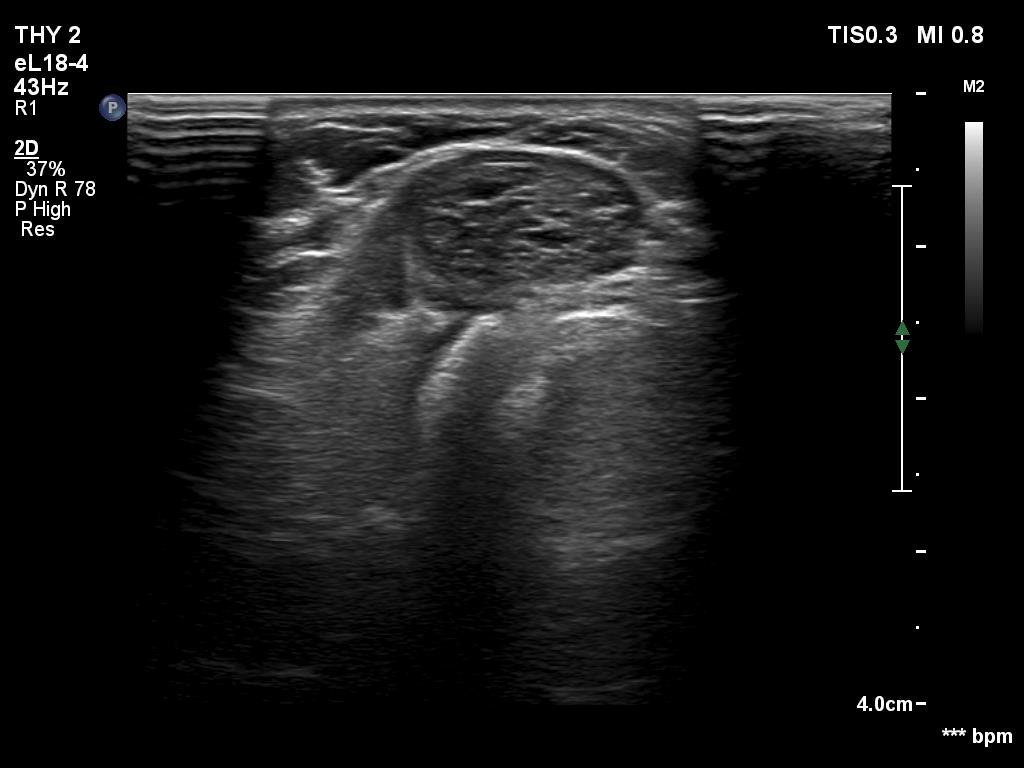

Ultrasonography. The thyroid was echonormal. There were several minimally hypoechoic discrete lesions in both lobes. Corresponding to the palpable nodule, a mixed, solid-cystic nodule was found which had spongiform areas. The solid part was minimally/moderately hypoechoic. The lesion did not show halo and presented neither intranodular nor perinodular blood flow.

Although the nodule belongs indeed to TIRADS 4 lesions, the risk of malignancy is practically zero in nodules with such presentation. This is probably an evolving spongiform cyst. A significant proportion of solid area has been already disappeared.